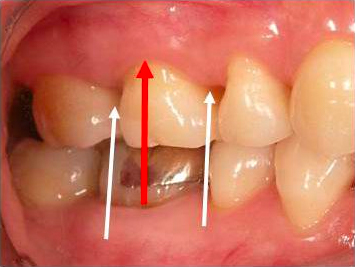

• 歯周疾患の診査 根分岐部病変の診査